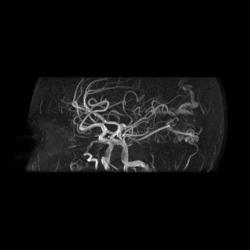

Артерио-венозная мальформация сосудов головного мозга.

3D TOF

При МР-ангиографии в режиме 3D TOF и 2D-TOF SPGR без применения контрастирующих веществ:

- определяется клубок расширенных и извитых патологических сосудов, получающих артериальную кровь из средней оболочечной артерии (ветвь наружной сонной артерии),  последняя расширена, из средней мозговой артерии и из задней мозговой артерии, эти артерии также шире, чем артерии контрлатеральной стороны. Дренирующие вены впадают в область стока синусов, а также в задний отдел верхнего сагиттального синуса

- дополнительно отмечены расширенные и извитые экстракраниальные сосуды, преимущественно под правой половиной задней черепной ямки.